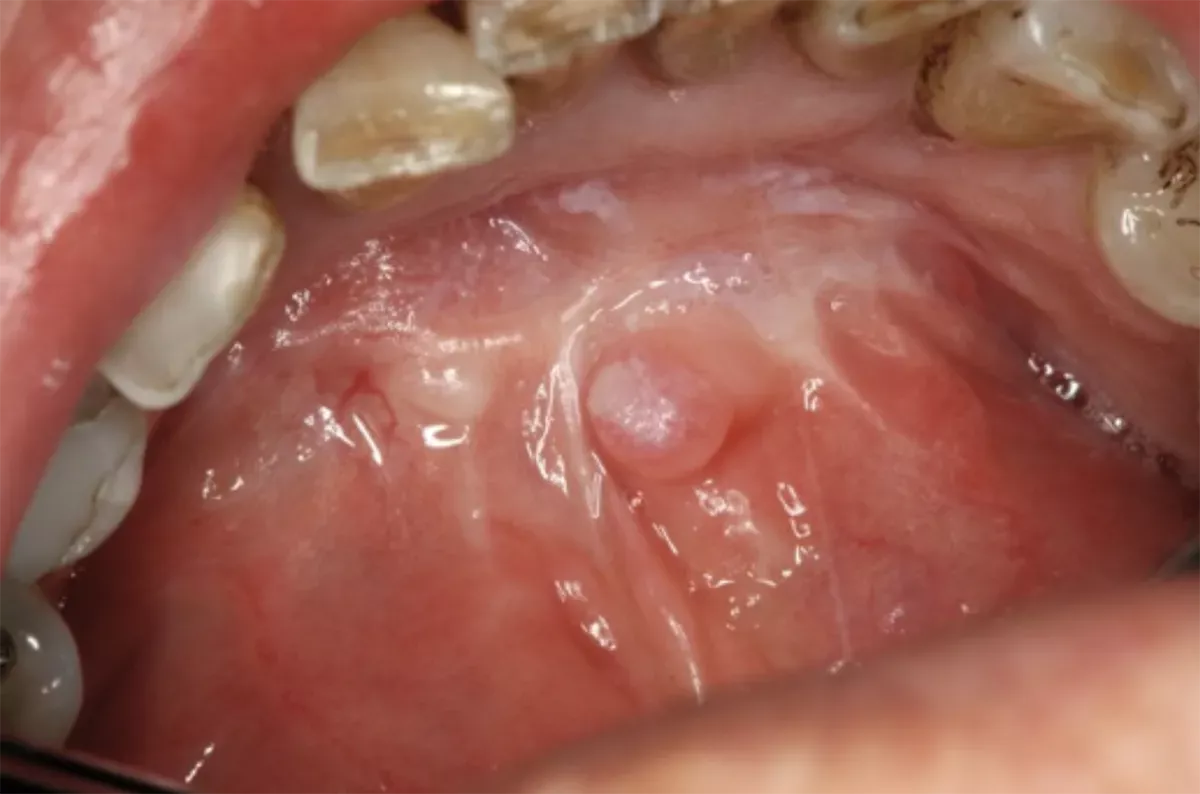

What does floor of the mouth cancer look like?

The following images provide a rough idea of what floor of the mouth cancer actually looks like. Note, however, that every tumour appears different. If you detect a suspicious spot on the floor of your mouth, have it checked by a doctor to rule out floor of the mouth cancer – regardless of whether it is a lump, an ulcer, a white or red patch or a sore. Aphthae can also look very similar but typically resolve on their own after one to two weeks without the need for treatment. If the affected area fails to heal, it is best to go and see a health care professional.